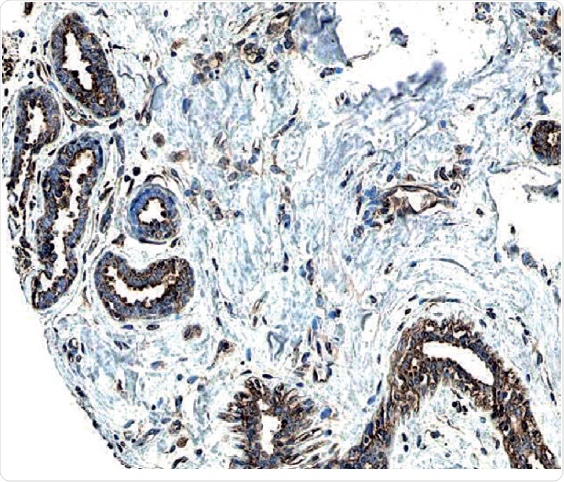

ErbB2/Her2 in Human Breast Cancer Tissue

Figure 2: ErbB2/Her2 in Human Breast Cancer Tissue.

ErbB2 expression detected in paraffin-embedded sections of human breast cancer tissue. The ERBB2/HER2 gene is commonly amplified or overexpressed in breast cancer. The receptor is visualized here as brown staining using a Rabbit Anti-Human Phospho-ErbB2 Affinity-purified Polyclonal Antibody (R&D Systems, Catalog #AF4438). Hematoxylin counterstain in blue.